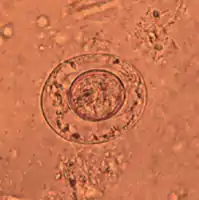

An egg of dwarf tapeworm

As its name implies (Ancient Greek: νᾶνος, nānos – dwarf), it is a small species, seldom exceeding 40 mm long and 1 mm wide. The scolex bears a retractable rostellum armed with a single circle of 20 to 30 hooks. The scolex also has four suckers, or a tetrad. The neck is long and slender, and the segments are wider than long. Genital pores are unilateral, and each mature segment contains three testes. After apolysis, gravid segments disintegrate, releasing eggs, which measure 30 to 47 µm in diameter. The oncosphere is covered with a thin, hyaline, outer membrane and an inner, thick membrane with polar thickenings that bear several filaments. The heavy embryophores that give taeniid eggs their characteristic striated appearance are lacking in this and the other families of tapeworms infecting humans. The rostellum remains invaginated in the apex of the organ. Rostellar hooklets are shaped like tuning forks. The neck is long and slender, the region of growth. The strobila starts with short, narrow proglottids, followed with mature ones.